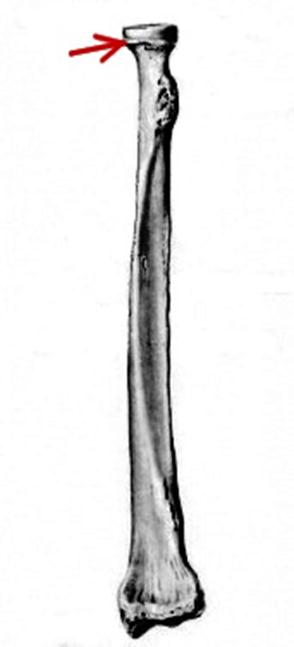

S: На рисунке – ### (латинский язык).

S: Стрелкауказывает на...

S: Стрелкауказывает на...

S: Стрелкауказывает на...

S: Стрелкауказывает на...